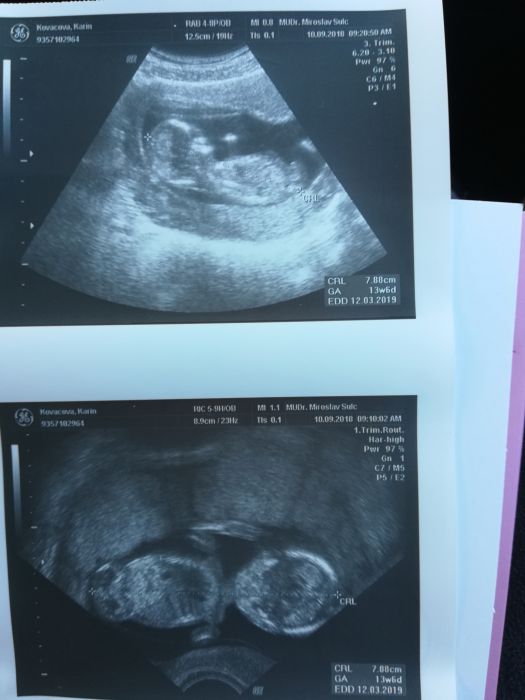

Přikládám foto ze včera a mého mini bříška